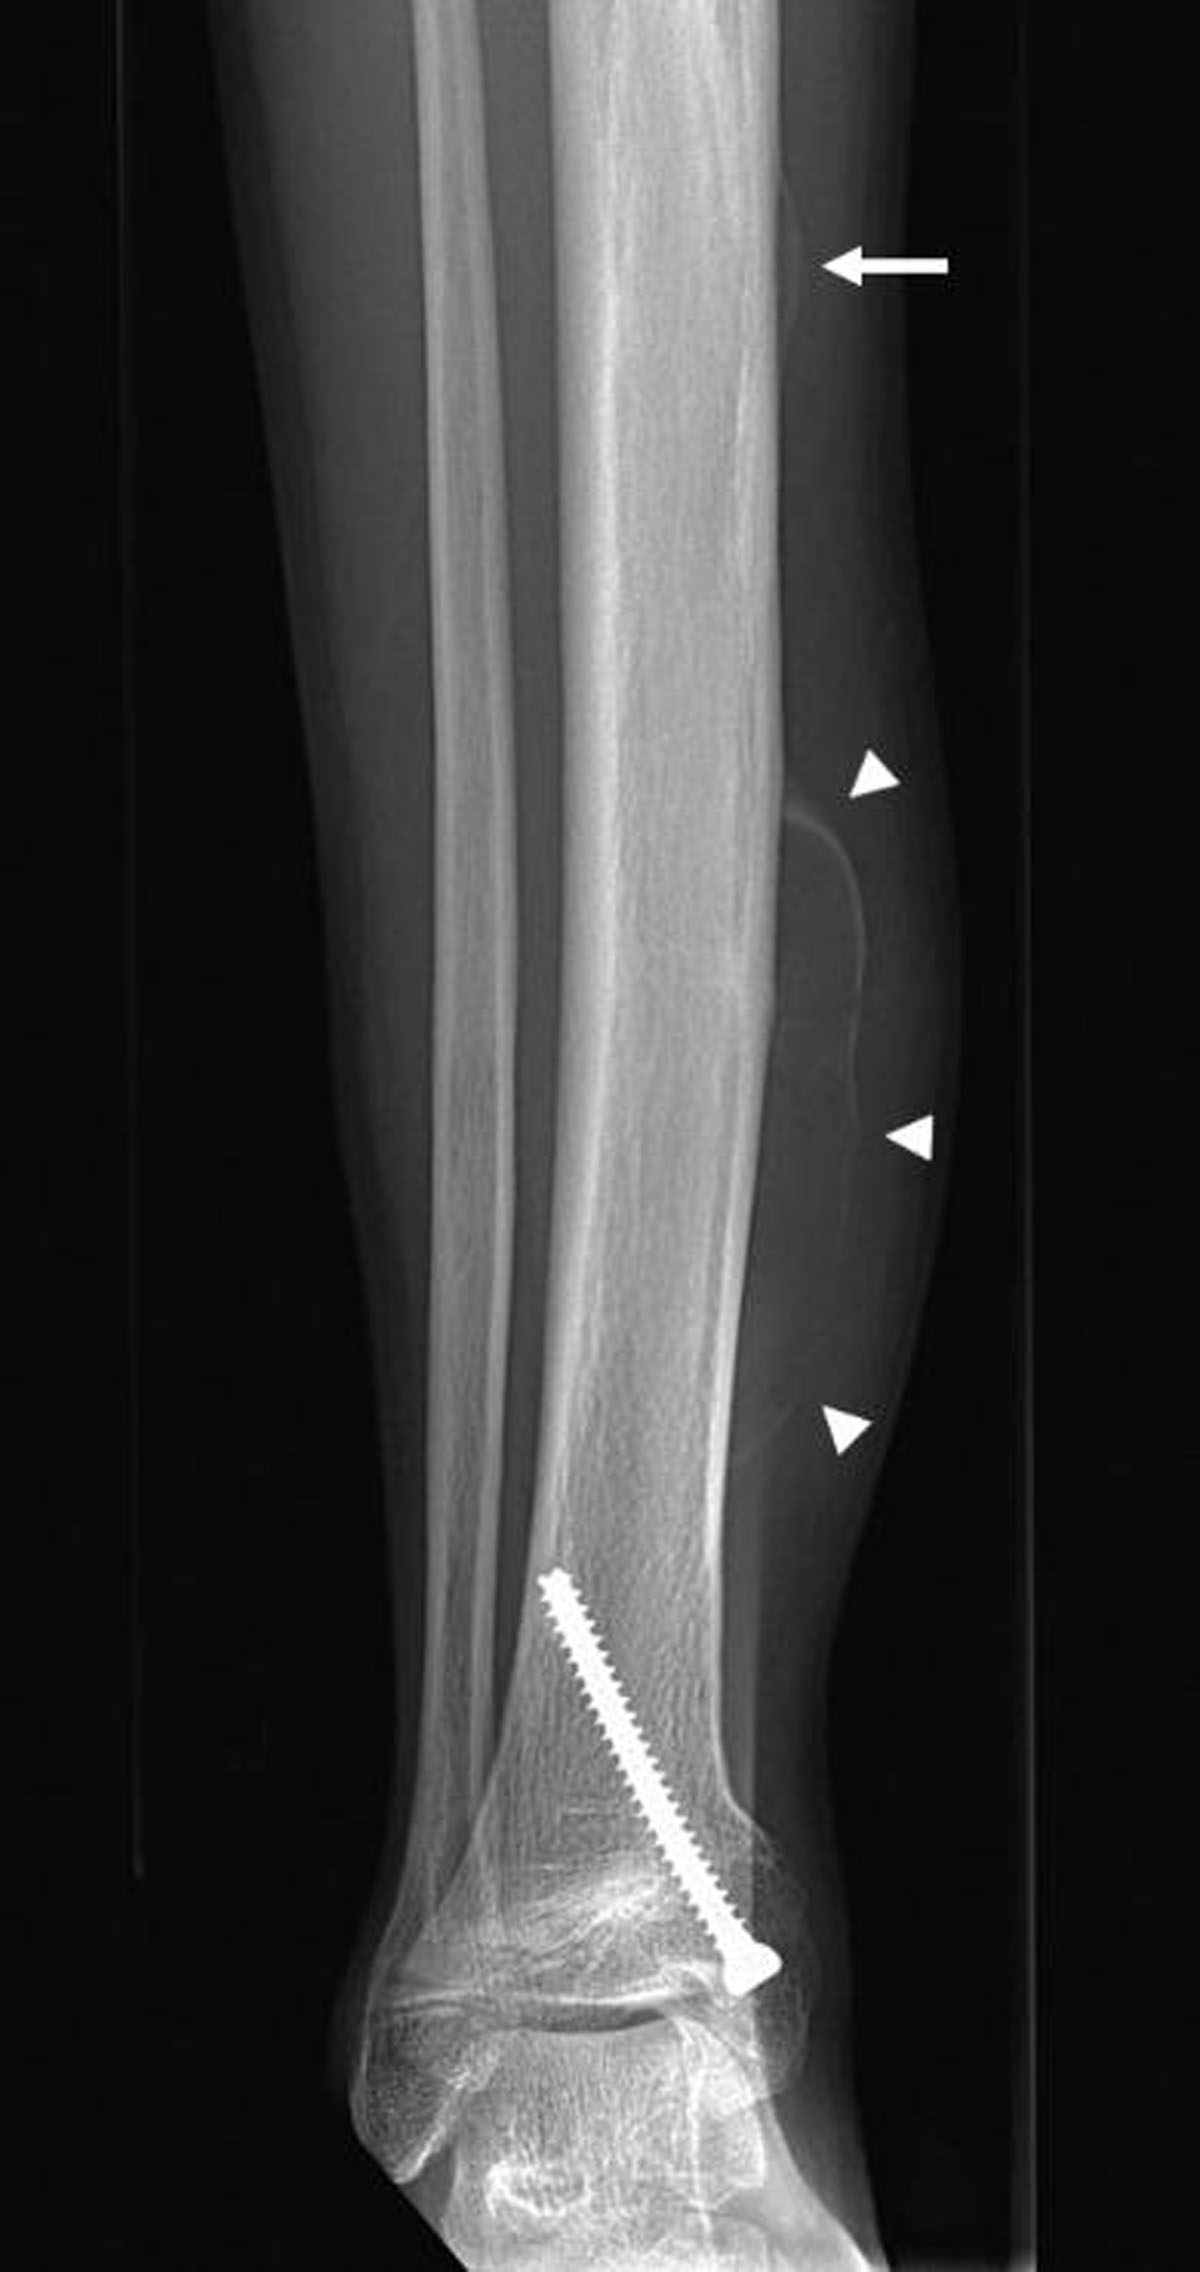

Radiographs (Figure 1) demonstrated a soft tissue swelling on the medial side of the tibial shaft outlined by a thin calcified rim (arrowheads). A smaller, similar lesion could be seen more cranially (arrow). Ultrasound (US) (Figure 2A-C) showed a subperiosteal collection (circle) with an internal fluid-fluid level (arrow) as well as calcification of the surrounding periosteum. The calcified periosteum is surrounded by a heterogeneous, vascularized soft tissue cuff (arrowheads). MRI (Figure 3A-D) demonstrated a subperiosteal collection with signal properties of a chronic hematoma (triangle): T1/T2-isointense in the periphery of the lesion but T1-iso/T2-hyperintense in the centre (Figure 3C and 3A, respectively, for T1- and T2-weighted imaging). Moreover, there was the additional finding of a T2-hyperintense, T1-isointense, fat-poor (Figure 3B), enhancing tissue (star in Figure 3D), located medially and posteriorly with respect to the hematoma, corresponding to the described soft tissue cuff on US. These MRI features were suggestive of a plexiform neurofibroma of the saphenous nerve, that has caused an ossifying subperiosteal hematoma due to chronic erosion of the tibial cortex. Note the smooth cortical thinning on MRI (dashed arrow), the mass effect exerted on the tibialis posterior and flexor digitorum muscles as well as the surrounding soft tissue oedema.

Figure 1